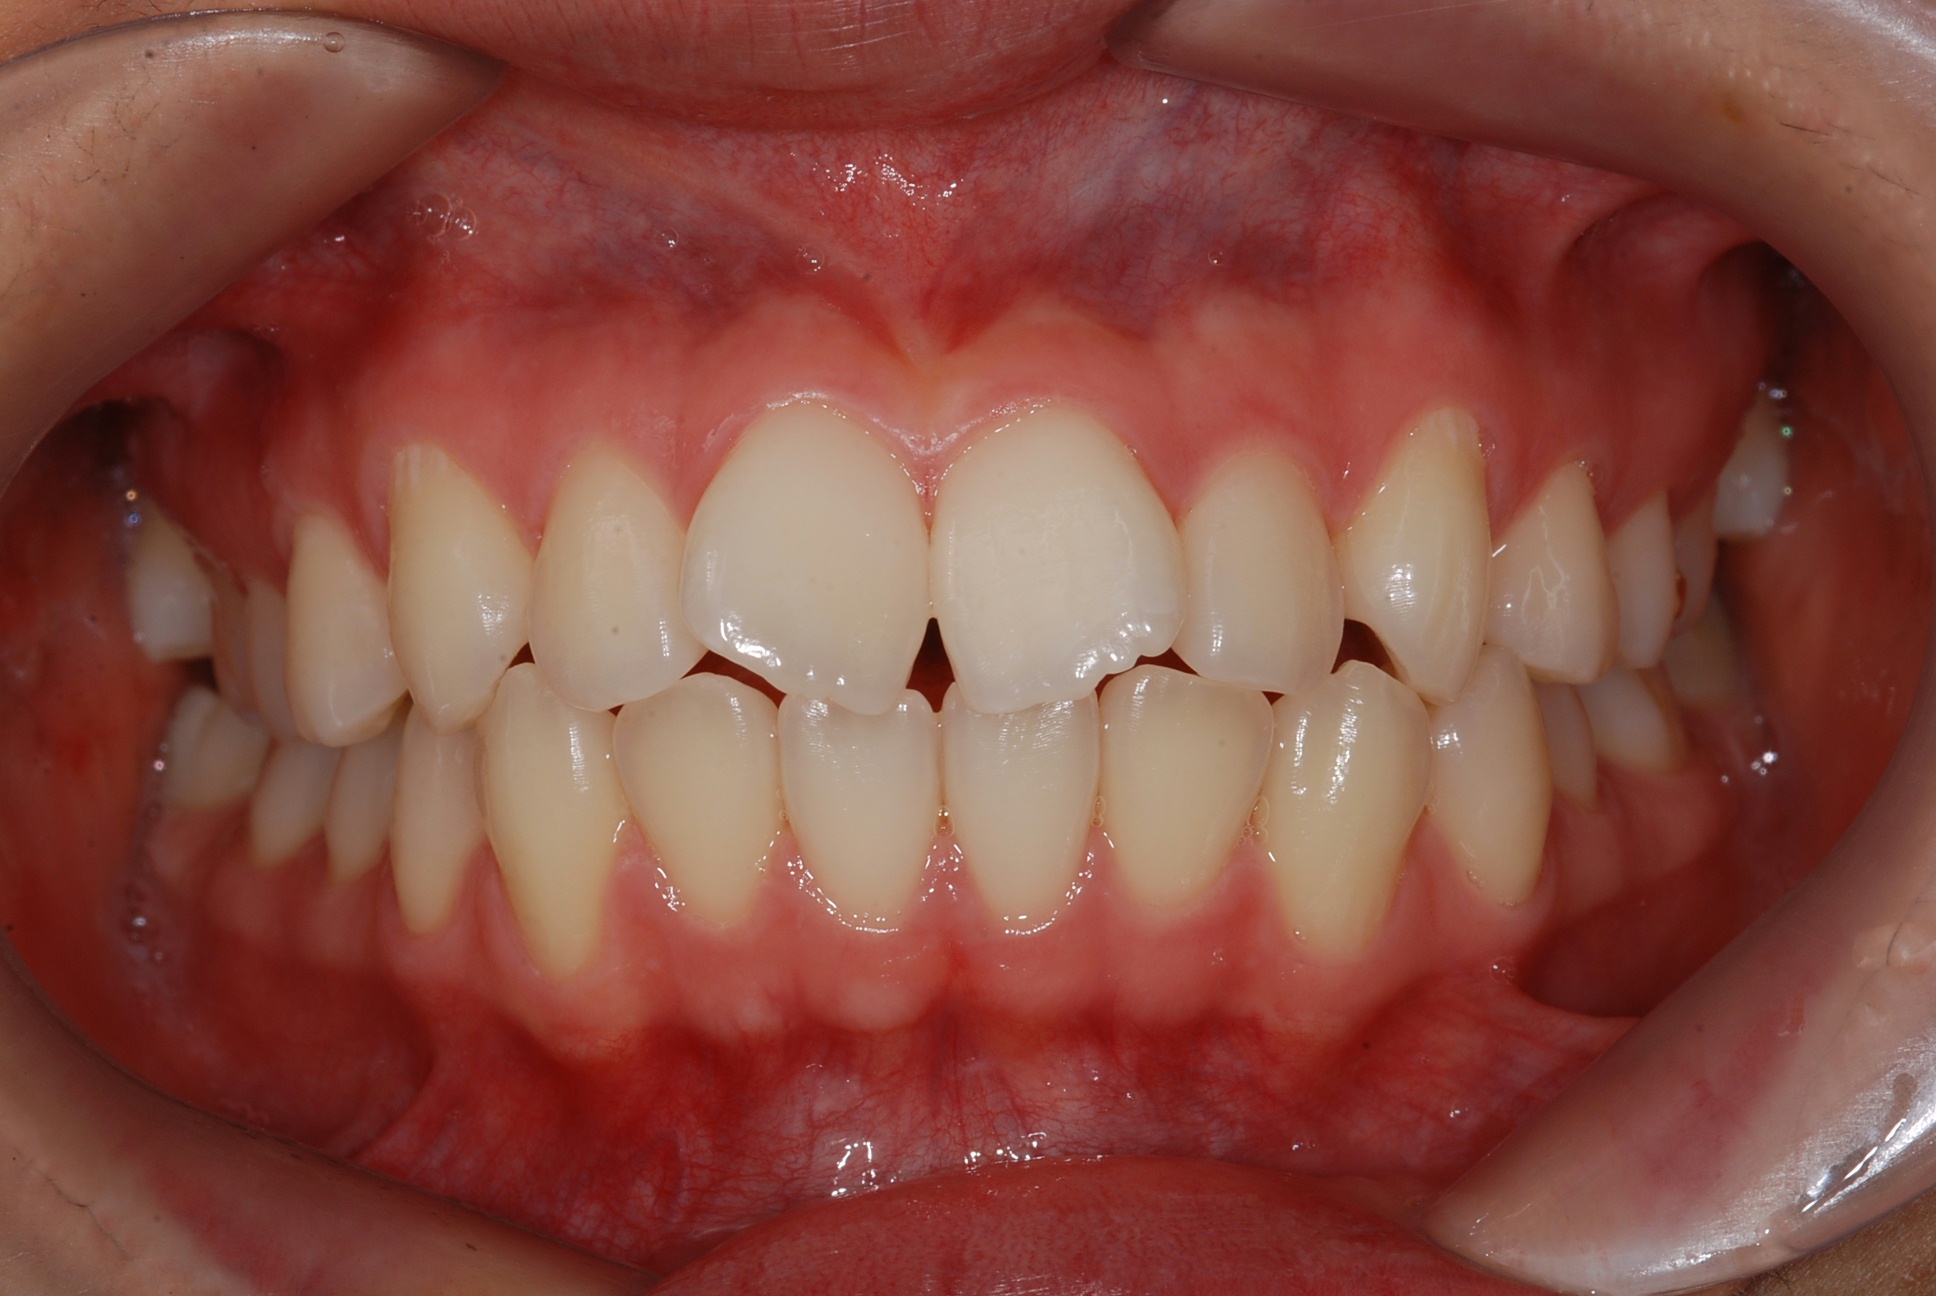

치료 전 사진입니다.